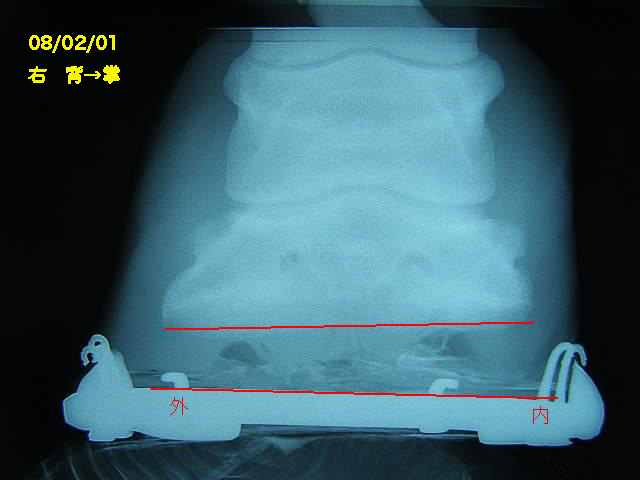

今回の左前肢

ラメラーウェッジがだいぶ取り除かれ、蹄が蹄壁にきちんとくっついて生えてきているのが確認できてホッとしました。